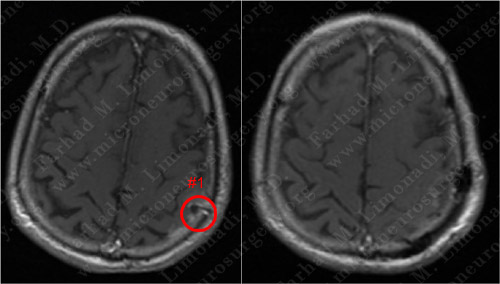

Post-Op Imaging

Before Operation Afer Operation

Post-op MRI shows radiographic resection of the first tumor.

Before Operation After Operation

Post-op MRI shows radiographic resection of the second tumor as well.